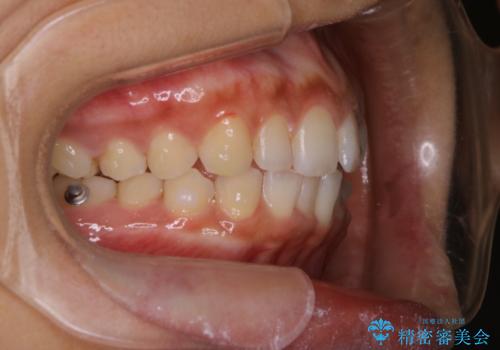

インビザライン治療中には、歯の表面にアタッチメント(効率的に歯の移動をするもの)を設定します。そのため歯ブラシでは届きにくい細かい部分などに、歯石や着色がついてしまうことがあります。着色などを放置していると、着色なのか、虫歯なのかの判別もしずらく正確にお口の中の状態を診断できません。

矯正治療中も定期的に歯科医院にてPMTCを受けて、お口のケアを行うことをおすすめします。

- インビザラインでの矯正治療中に、着色や汚れが気になるとのことでした。PMTC60分コースを行いました。